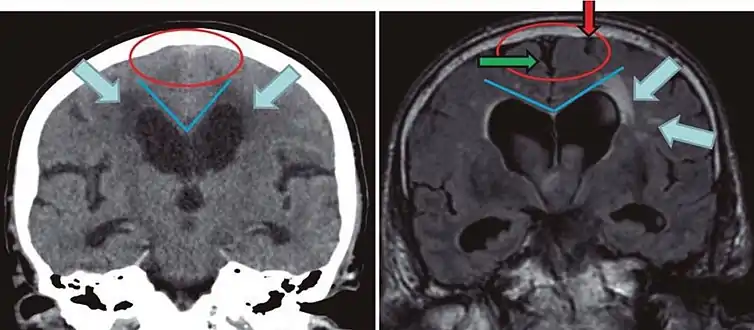

- Imaging from magnetic resonance imaging (MRI) or computed tomography (CT) is needed to demonstrate enlarged ventricles and no macroscopic obstruction to cerebrospinal fluid flow. Imaging should show an enlargement to at least one of the temporal horns of lateral ventricles, and impingement against the falx cerebri resulting in a callosal angle ≤ 90° on the coronal view, showing evidence of altered brain water content, or normal active flow (which is referred to as "flow void") at the cerebral aqueduct and fourth ventricle.

Normal pressure hydrocephalus | Brain atrophy | |

---|---|---|

Preferable projection | Coronal plane at the level of the posterior commissure of the brain. | |

Modality in this example | CT | MRI |

CSF spaces over the convexity near the vertex (red ellipse ![]() | Narrowed convexity ("tight convexity") as well as medial cisterns | Widened vertex (red arrow) and medial cisterns (green arrow) |

Callosal angle (blue V) | Acute angle | Obtuse angle |

Most likely cause of leucoaraiosis (periventricular signal alterations, blue arrows ![]() |

Transependymal cerebrospinal fluid diapedesis | Vascular encephalopathy, in this case suggested by unilateral occurrence |